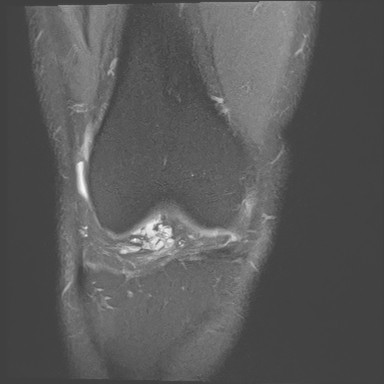

Figure 1 for case Orthovisc injections

Figure 1